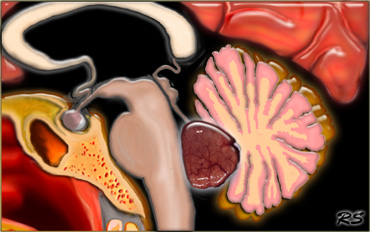

Pineal region

Common pineal region tumors are listed in the table on the left.

On the left a tumor located in the pineal region.

Based on these images the differential diagnosis would include:

• Meningioma

• Pineocytoma

• Germ Cell Tumor

This happened to be a meningioma.

On the left are typical images of a ruptured pineal region dermoid.